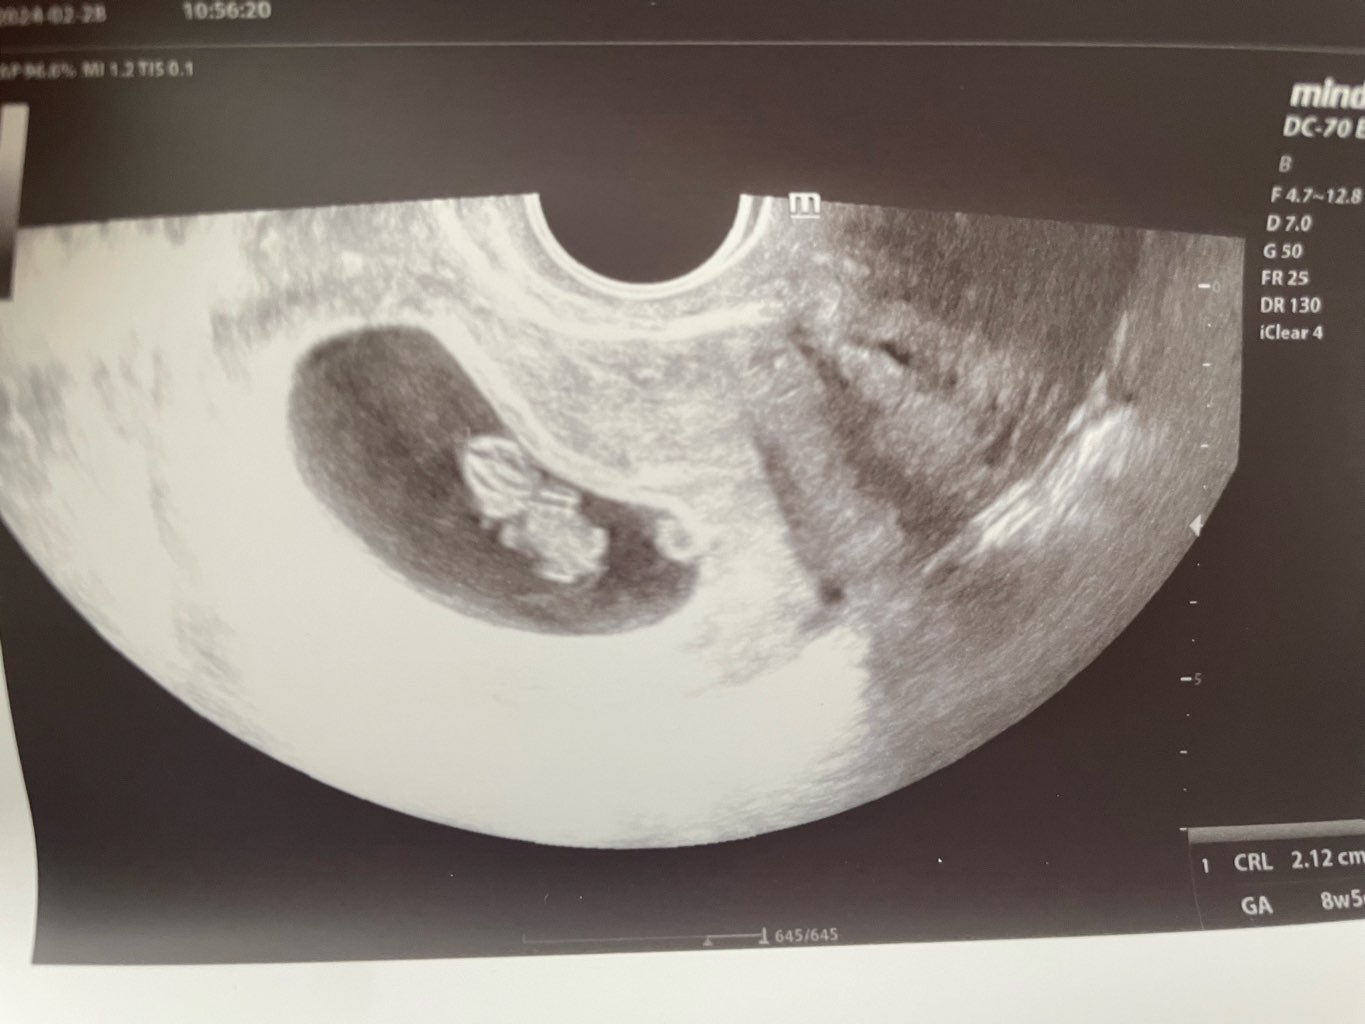

Już ma jakieś kształty

Załączniki

• IMG_2841.jpeg

IMG_2841.jpeg

111,1 KB · Wyświetleń: 88